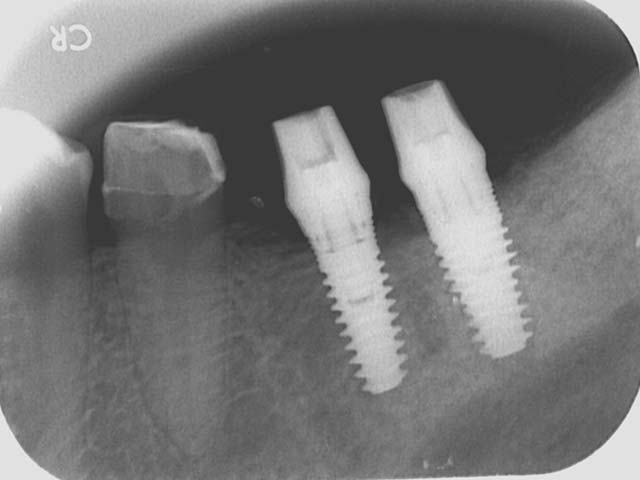

牙橋嚴重蛀牙,即拔即種,避免二次傷口 首頁 案例分享 人工植牙 牙橋嚴重蛀牙,即拔即種,避免二次傷口 多年前製作之牙橋,因為二度齲齒,導致支台齒蛀蝕,而需重新製作 牙橋支臺齒嚴重蛀牙 STEP1.拔除殘根並植入兩根植牙 STEP2.骨粉填補缺損骨頭缺陷 STEP3.三個月後,準備製作正式假牙 STEP4.正式假牙完成